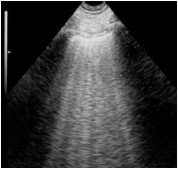

Assinale a opção que apresenta a imagem de ultrassonografia pulmonar compatível com a descrição do quadro acima.